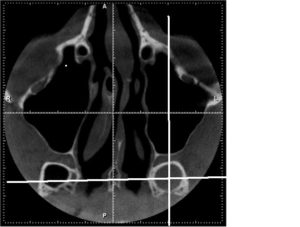

- информативнее других методов обнаруживают сфеноидит компьютерная или магнитно-резонансная томография;

- при недоступности КТ и МРТ выполняется рентгенологическая диагностика;

КТ — исследование пазухи с помощью рентгеновского излучения. КТ позволяет выявить аномалии синуса, степень поражения слизистой. При исследовании с помощью КТ определяется уровень гноя в пазухе.

Ещё более информативным методом диагностики является МРТ — она выявляет послойные поражения, которые могут быть не замечены на КТ.

Единственными методами, которые наверняка могут определить сфеноидит, являются компьютерная томография (КТ) или магнитно-резонансная томография (МРТ) –

Нередко, особенно при хроническом течении, врачи прибегают к проведению компьютерной томографии. С ее помощью удается послойно оценить строение носа и придаточных его пазух. Главное преимущество этого метода – это возможность определить размер соустий, который влияет на частоту рецидивов заболевания и отражается на тактике лечения.